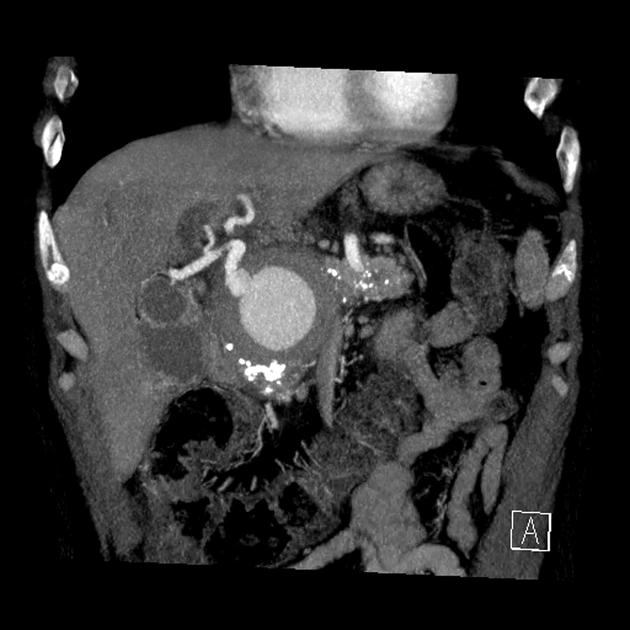

• Phình động mạch tạng (Visceral Artery Aneurysms - VAA)

• Phình động mạch thận (Renal Artery Aneurysm - RAA)

• Giả phình động mạch thận (Renal Artery Pseudoaneurysm)